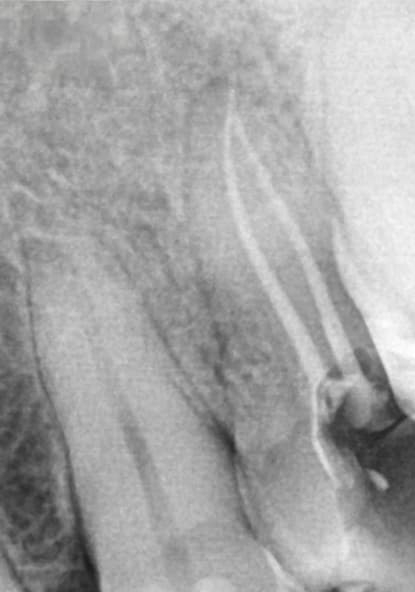

In narrow, curved, or partially calcified canals, progression may be limited. It is advisable not to force the instrument but to increase coronal flaring or establish a manual glide path to size 20 before reattempting apical progression. In most molar cases, however, the described glide path–free crown-down technique allows safe and effective shaping (Figure 4 and Figure 5).